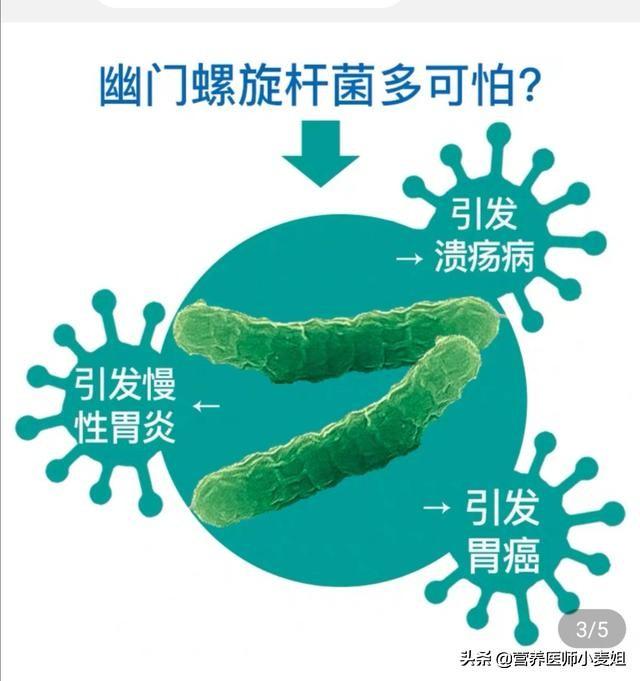

4.胃潰瘍

中国における胃潰瘍の主な原因はヘリコバクター・ピロリ菌の感染であり、胃潰瘍患者のうち胃癌に移行するのはごく一部であるが、この感染修復の繰り返しが癌の主な原因の一つである。したがって、胃潰瘍の患者は定期的に胃カメラ検査を受け、早期胃癌を除外する必要がある。

炎症性で過形成性の胃ポリープは、ヘリコバクター・ピロリ菌の感染と密接な関係があり、ピロリ菌を駆除する内服薬を服用すると、ほとんどの人の胃ポリープが縮小または消失する。

胃がんにつながる可能性のある病気:

- ヘリコバクター・ピロリ感染を合併した胃炎

多くのがんの中でも、肝臓がん、胃がん、子宮頸がんは感染症と密接な関係があり、それぞれ90%の相関関係があるB型およびC型肝炎ウイルス、ヘリコバクター・ピロリ菌、ヒト乳頭腫ウイルス。これら4つの病原体は、対応する前癌病変を引き起こす可能性がある。

- 慢性萎縮性胃炎と胃潰瘍は胃癌の前癌病変である。この2つの病気には共通の原因があり、ヘリコバクター・ピロリという名前の小さな小さな細菌である。

ピロリ菌の最も一般的な診断方法は、「泡を吹く」検査、すなわちC13およびC14呼気検査であり、簡単で便利、苦痛がなく、精度が高い。最も一般的な診断方法は "泡を吹く "検査、すなわちC13とC14の呼気検査で、簡単で便利、痛みもなく正確です。 4剤併用療法は、1種類の酸抑制剤+2種類の抗生物質+1種類のビスマスである。胃がんの早期発見には定期的な胃カメラが不可欠。